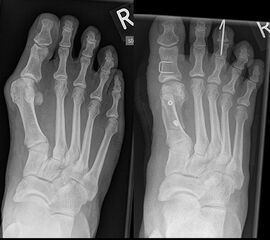

An erster Stelle der bildgebenden Diagnostik steht die konventionelle Röntgendiagnostik. Der betroffene Fuß wird dabei unter Belastung in 3 Ebenen dargestellt. Beurteilt werden der Intermetatarsale-I-Winkel (IM-Winkel), der Hallux valgus Winkel (HV-Winkel), die Lage der Sesambeine, der Arthrosegrad im MTP I Gelenk und ein mögliches plantares Klaffen „gapping“ im Tarsometatarsale-I Gelenk als Hinweis auf eine Gelenkinstabilität. Neben der reinen Beurteilung des Hallux valgus sollten immer auch die Kleinzehen beurteilt werden.

Zum Lesen der Bildbeschreibung und zur Vollansicht bitte das Bild anklicken. Bild: Markus Walther.